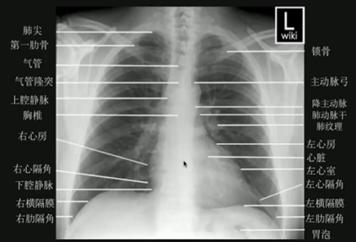

一、胸片基础解剖

阅读胸片需要多个视角,以下图示标识了正位及侧位胸片中各个解剖结构的位置。其中,应特别注意小儿胸腺这一特殊的解剖结构。

图1.正位(后前位)胸片解剖结构